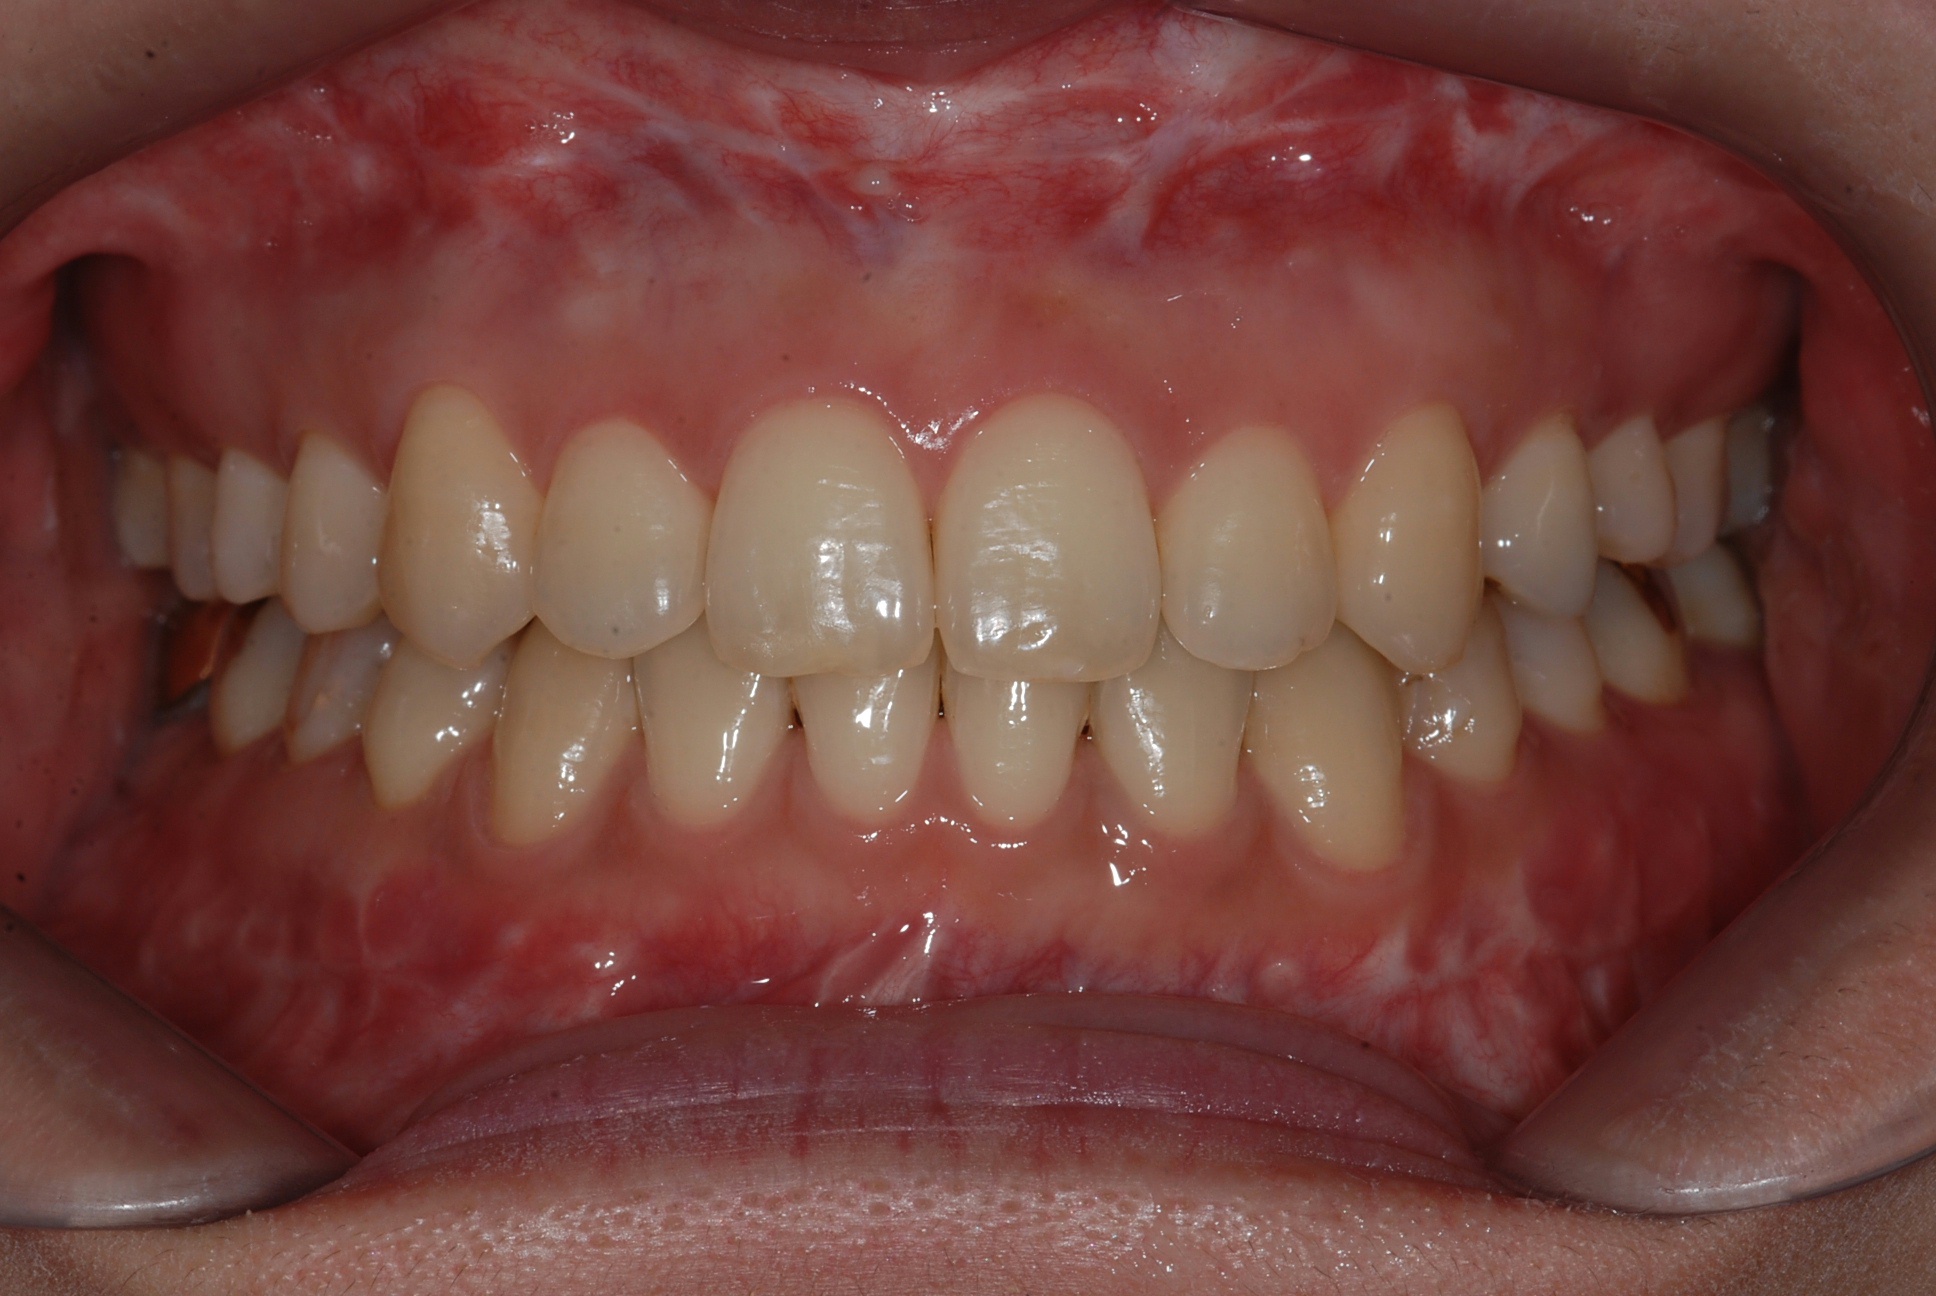

치료 후 사진입니다.